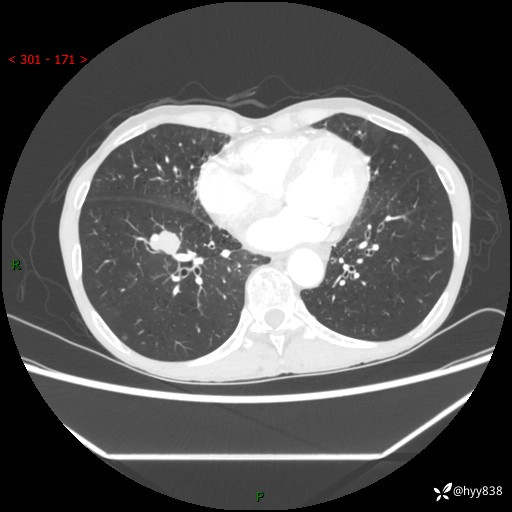

【现病史及既往史】:患者3天余前因既往肺气肿复查胸部CT发现“右肺下叶结节、双肺多发结节、双肺门及纵膈淋巴结增大”,平素偶有咳白色粘液痰,下肢乏力,无明显低热、盗汗、咯血、胸痛、喘气等不适,今为求明显结节性质遂来我院门诊就诊,门诊以“孤立性肺结节”收治入院。 起病以来,患者精神饮食睡眠一般,大小便正常,体力无明细变化,体重近年来较前下降。

【检查】:胸部CT增强